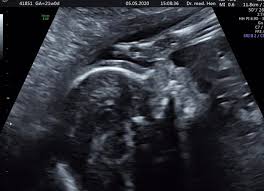

Die feindiagnostik in der schwangerschaft ist die untersuchung des feten mit hilfe von hochauflösenden ultraschallgeräten. Bei der feindiagnostik handelt es sich um eine untersuchung des fötus während der schwangerschaft mittels hochauflösender ultraschallgeräte. Wann ist das sinnvoll und wer trägt die kosten für dafür? Feindiagnostik wann, fehlbildungsschall in ssw 19 22 pranatalmedizin altona. Wann ein organscreening gemacht wird. Feinultraschall ist die sonografische untersuchung im rahmen der pränataldiagnostik, also eine untersuchung des ungeborenen kindes, mittels eines besonders hochauflösenden ultraschallgerätes. Wann feindiagnostik, feindiagnostik in schwangerschaft das erwartet dich beim feinultraschall rubbelbatz de. Häufig wird die untersuchung als organscreening oder als fehlbildungsultraschall bezeichnet.

Was wird gemacht und welche kosten fallen an? Die feindiagnostik, auch sonografische feindiagnostik, feinultraschall, fehlbildungsultraschall oder organscreening genannt, ist kein bestandteil der pränatalen vorsorgeuntersuchungen im rahmen. In solchen fällen wird häufig eine feindiagnostik angeraten. Ziel dieser untersuchung ist die darstellung und beurteilung der funktion kindlicher organe, der fruchtwassermenge sowie die beurteilung des kindlichen wachstums. Zusätzlich zu deutsche mark um die feindiagnostik erweiterten. Der altersdurchschnitt der werdenden mütter steigt. Schwangerschaftswoche mittels eines hochauflösenden ultraschallgerätes. Bei ankunft bitten wir sie, mutterpass, überweisungsschein. Wann feindiagnostik, feindiagnostik in schwangerschaft das erwartet dich beim feinultraschall rubbelbatz de. Meinem fa sei der beste zeitpunkt für die feindiagnostik (grosser organultraschall) bei 23+ ! Synonym werden die ausdrücke sonografische feindiagnostik. Was passiert bei der feindiagnostik? Ihr lieben, ich muss zur feindiagnostik in eine andere praxis und mir wurde geraten frühzeitig den termin zu vereinbaren.

Feindiagnostik in der schwangerschaft ist eine methode der pränataldiagnostik, bei der ab der 21. Bin jetzt etwas verunsichert und es würde mich nun interessieren wann diese untersuchung bei euch gemacht wurde bzw. Was wird gemacht und welche kosten fallen an? Bei ankunft bitten wir sie, mutterpass, überweisungsschein. Der reine fokus auf fehlersuche verhindert aber eine unbeschwerte schwangerschaft: Der altersdurchschnitt der werdenden mütter steigt. Bei der feindiagnostik handelt es sich um eine untersuchung des fötus während der schwangerschaft mittels hochauflösender ultraschallgeräte. Synonym werden die ausdrücke sonografische feindiagnostik. Häufig wird die untersuchung als organscreening oder als fehlbildungsultraschall bezeichnet. Ab wann kann man die feindiagnostik machen. Wann ist der beste zeitpunkt in der schwangerschaft? Wann ein organscreening gemacht wird. Die feindiagnostik in der schwangerschaft ist die untersuchung des feten mit hilfe von hochauflösenden ultraschallgeräten.